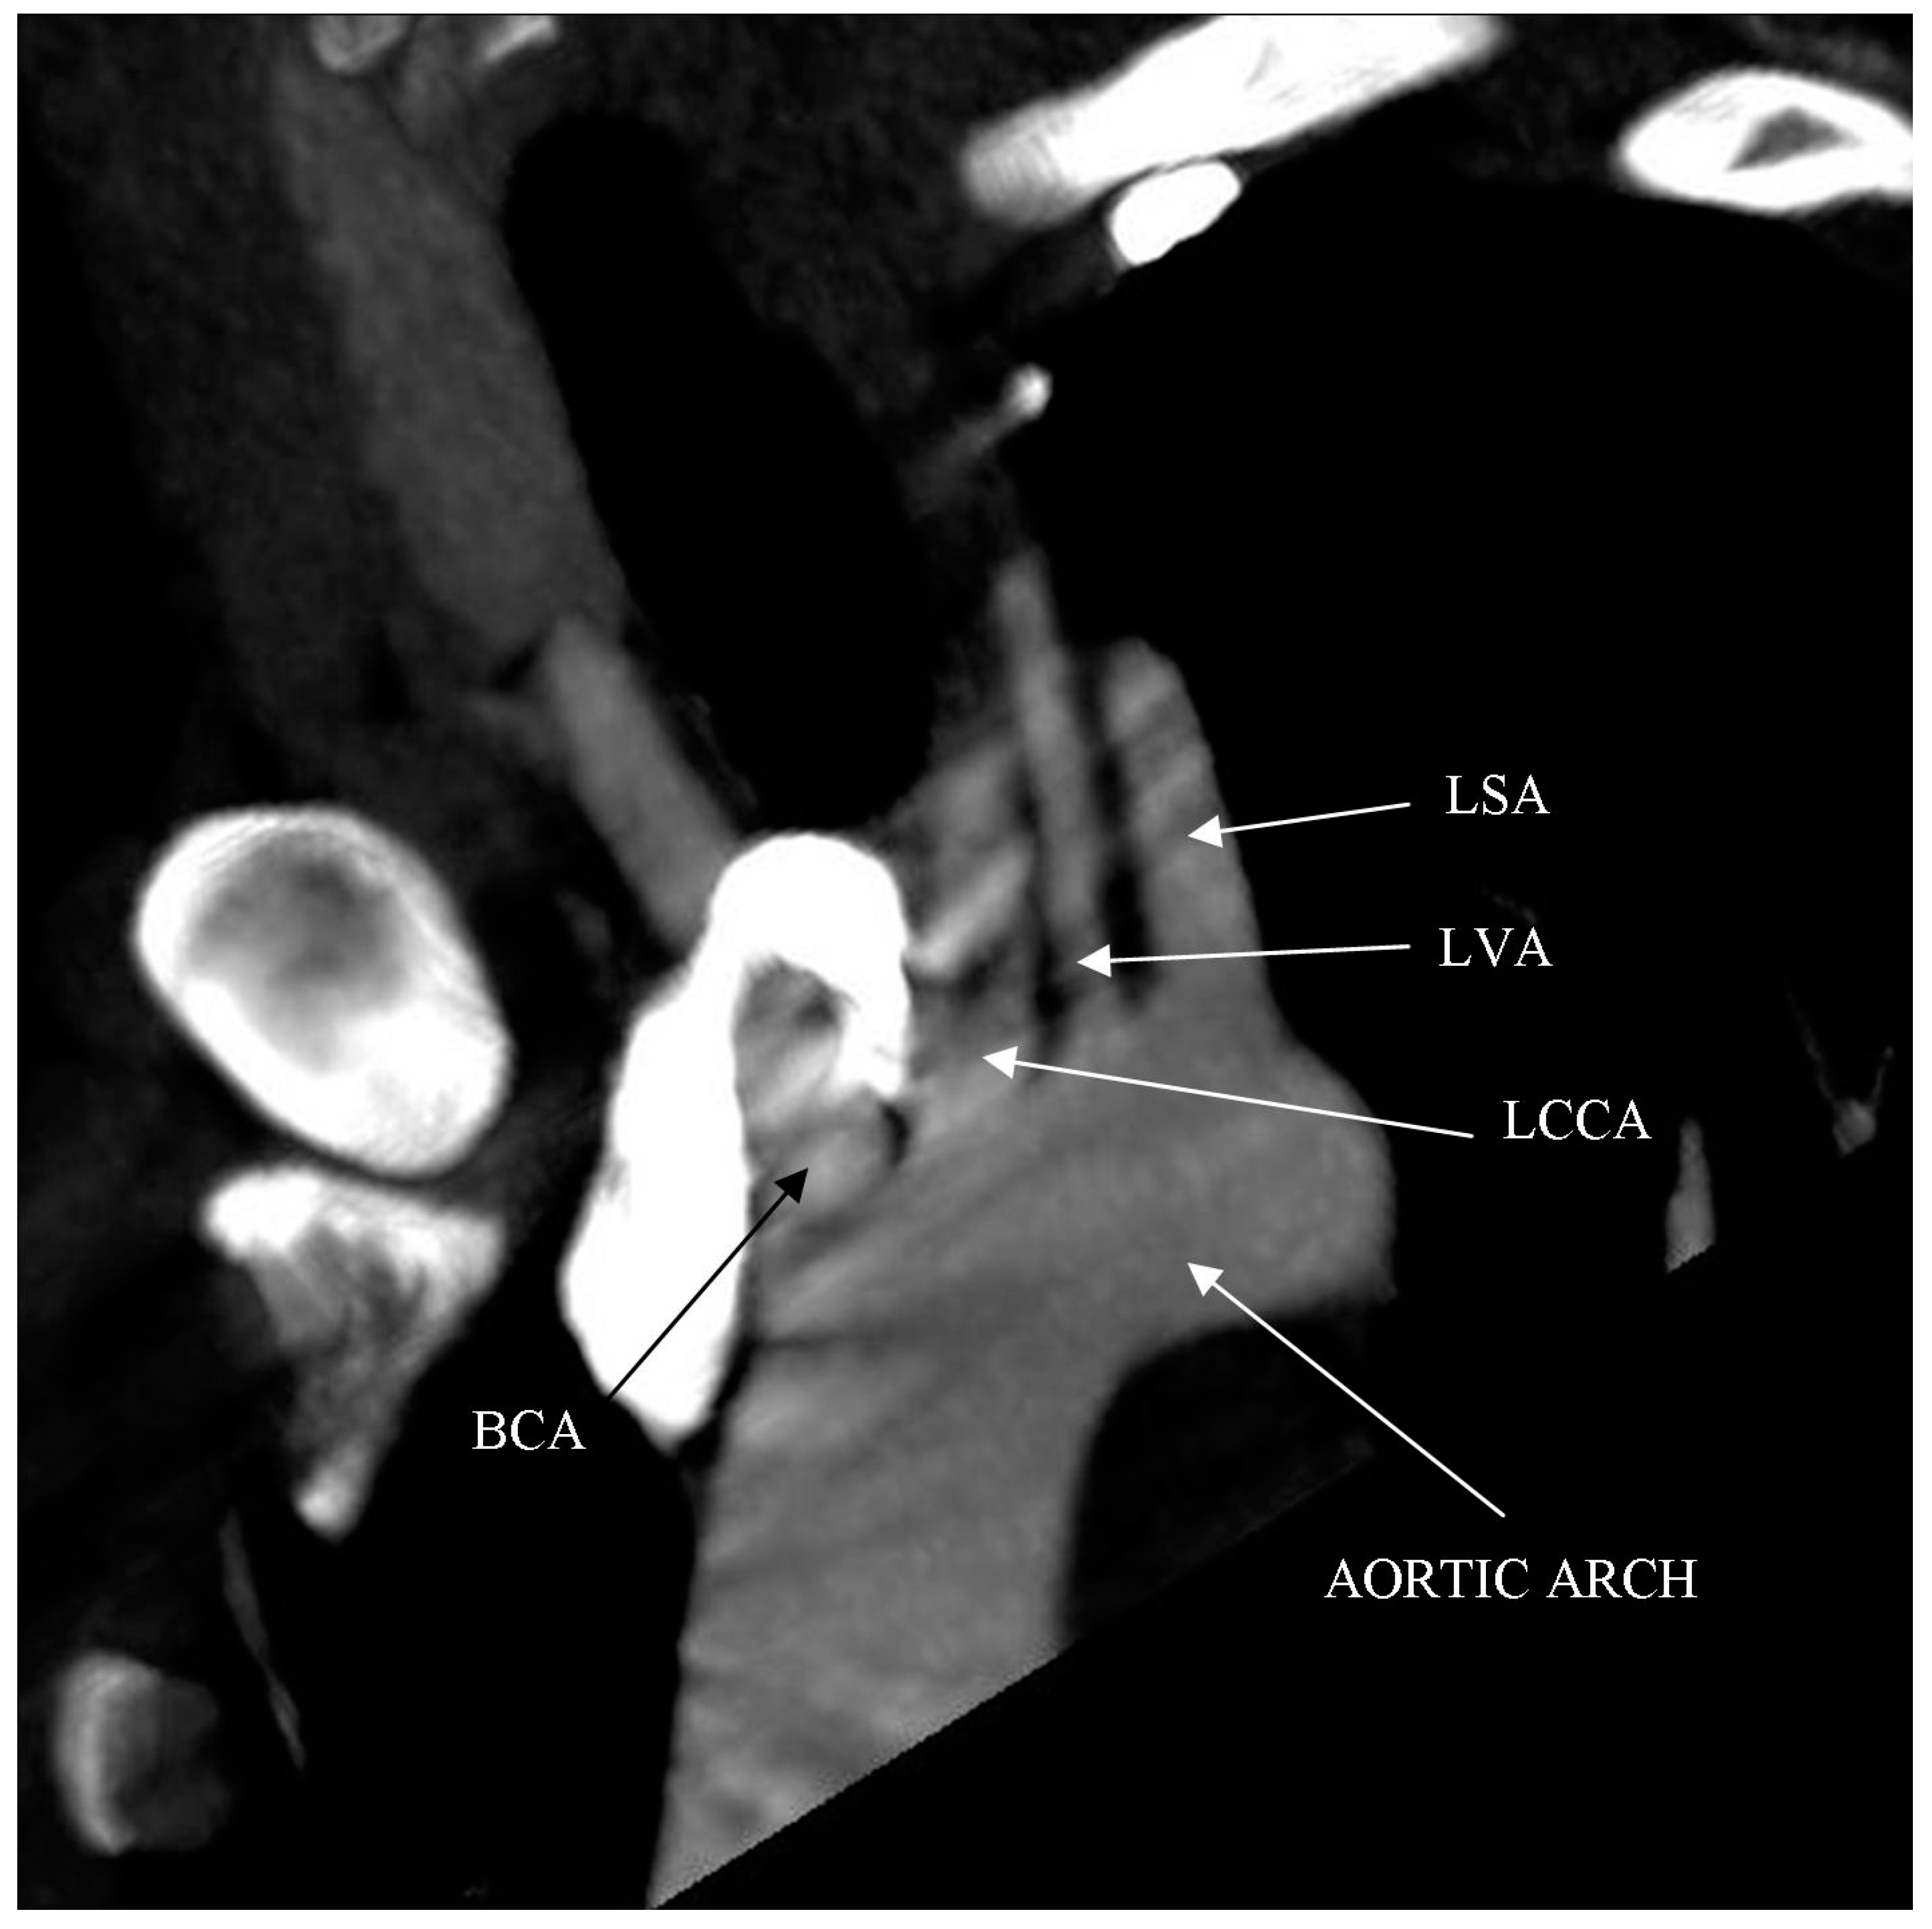

Computed tomography angiography (CTA) of the right upper limb was performed in 5.0- and 0.5-mm layers. The examination showed a non-dilated aortic arch with an independent left vertebral artery ostium between the ostia of the left common carotid artery and the left subclavian artery (Figure 1). Moreover, non-dilated arterial vessels of the right upper limb were visualized—the brachiocephalic trunk, the right subclavian artery, the right axillary artery, the right brachial artery, and the arteries of the right forearm. At the level of the distal epiphysis of the right humerus, just before the division of the brachial artery into the arteries of the forearm, a leakage of the contrast agent beyond the lumen was found, consistent with active bleeding from the injured brachial artery (Figure 2). At this level, a layered soft tissue hematoma was visualized around the brachial artery with approximate dimensions of up to 7.0 cm × 5.9 cm in cross-section and 8.4 cm in the longitudinal dimension (Figure 3). Within the soft tissue hematoma, a high-density, metallic foreign body up to about 0.7 cm in cross-sectional dimensions was localized (Figure 4).

Figure 1. Right upper limb computed tomography angiography. MIP reconstruction. Candy cane view. Independent left vertebral artery ostium between the ostia of the left common carotid artery and the left subclavian artery (vascular anatomic variant).